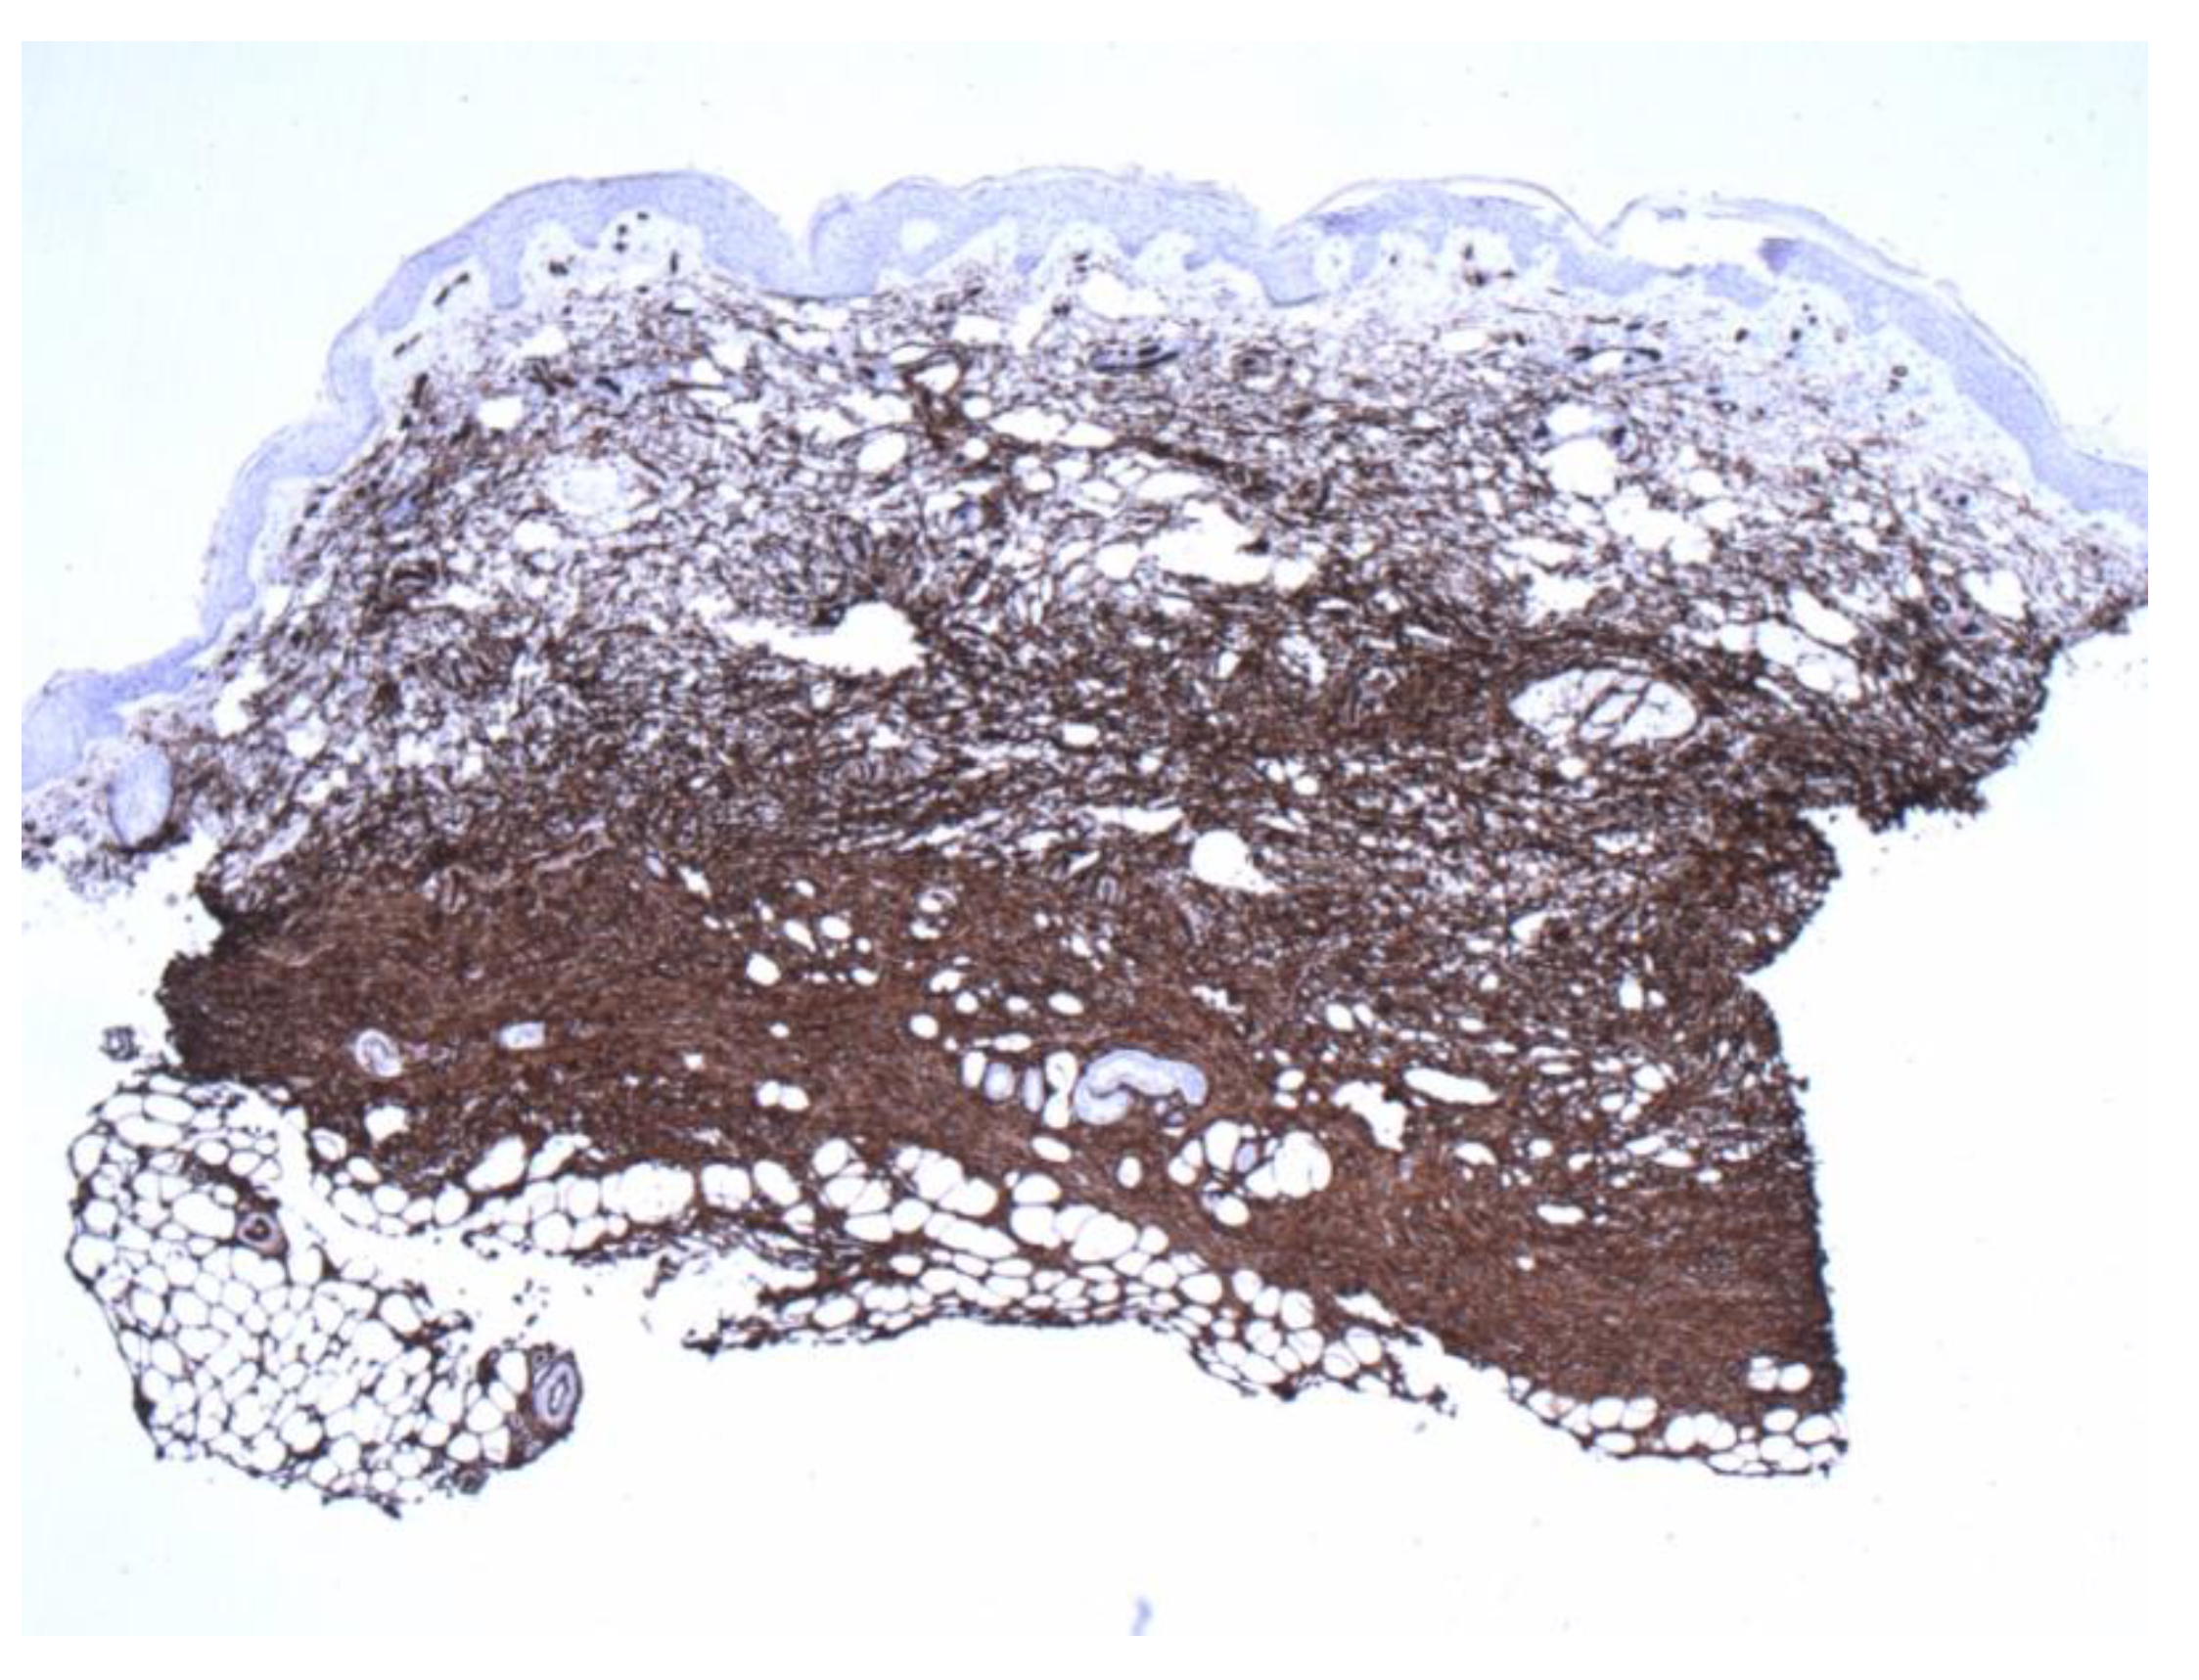

Figure 4.

Positive CD34 staining with contrasting sparse-superficial and dense-deeper areas (4×).